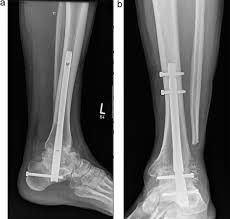

Am Tag selbst werde ich am Morgen aufgenommen, dann folgt eine Blutentnahme und das Gespräch mit der Anästhesie. Um 13:00 Uhr beginnt die Operation, die mehrere Stunden dauern wird. Geplant ist ein retrograder tibio-talocalcanealer Nagel (TTC). Konkret bedeutet das, dass eine Titanstange vom Fersenbein bis zum Schienbein eingesetzt wird, um die Stabilität zu sichern. Die beiden betroffenen Gelenke, das untere Sprunggelenk (USG) und das obere Sprunggelenk (OSG), werden dauerhaft versteift. Die Beweglichkeit der Sprunggelenke ist damit weg, aber da ich seit über einem Jahr ohnehin nicht mehr abrollen kann, wird die Umstellung weniger drastisch ausfallen, als es klingt.

Der Fuss wird neu positioniert, und der Raum, in dem einst mein Sprunggelenk war, das durch die Staphylokokken-Infektionen praktisch zerstört wurde, wird mit Knochenmaterial aufgefüllt. Dieses wird entweder aus meinem Becken entnommen oder, falls nötig, aus einer Knochenbank bezogen. Eigenknochen hat den Vorteil, dass mein Körper ihn in der Regel besonders gut akzeptiert, kein Risiko eines “biologischen Missverständnisses”.